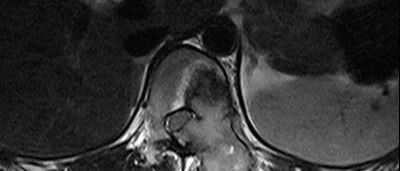

骨巨细胞瘤!

医学影像  yxyx-app  医学影像APP,打造伴随医生快速成长的影像学习社区。与影像园(Xctmr.com)一起提供最全面的影像案例库、基础(解剖、病理、影像诊断)知识、影像技术及考题等,为医生提供最佳的医学影像参考。【所属科室】骨科【基本资料】患者,女,30岁【主诉】腰背部酸痛1月【现病史】患者于1个月前无明显诱因出现腰背部酸痛,渐进性加重。【体格检查】...